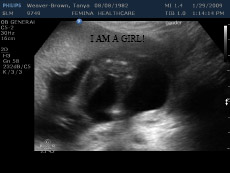

Baby was cooperating and was showing off so nicely that the ultrasound technician was able to confirm that we are,

indeed, expecting a girl. Ever since Dr. Hsiao gave us a 70% chance at 12 weeks, we were not thinking about

anything else. Don’t get me wrong, we would have been happy either way but for some reason, my husband and I

knew for years, that we were going to have a girl. Above, you can see an ultrasound picture with the buttocks and

two legs with “nothing in between them” and next to it a quick recording of her moving.